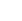

口内情况:下颌缺牙3颗,上颌缺牙2颗,合计缺牙5颗

主治医生:郑苍尚教授

种牙方案:数字化微创无痛种植 情况类似,咨询方案

种牙方案:通过德国KAVO锥形束CT检查缺牙处牙槽骨的骨质密度、厚度,并分析牙周口腔健康后,对苏伟采用“微创无痛种植”恢复牙咬合功能……[查看方案]

口腔状况:上颌缺牙2颗,下颌缺牙3颗

治疗方案:全数字化精确种植牙

主诊医生点评:根据术前CT显示的牙槽骨数据和口腔健康情况分析,微创无痛种植能有效恢复牙咬合功能,仅3-4毫米微小切口,即可完成种植,减少肿痛和出血量,种植成功率更高